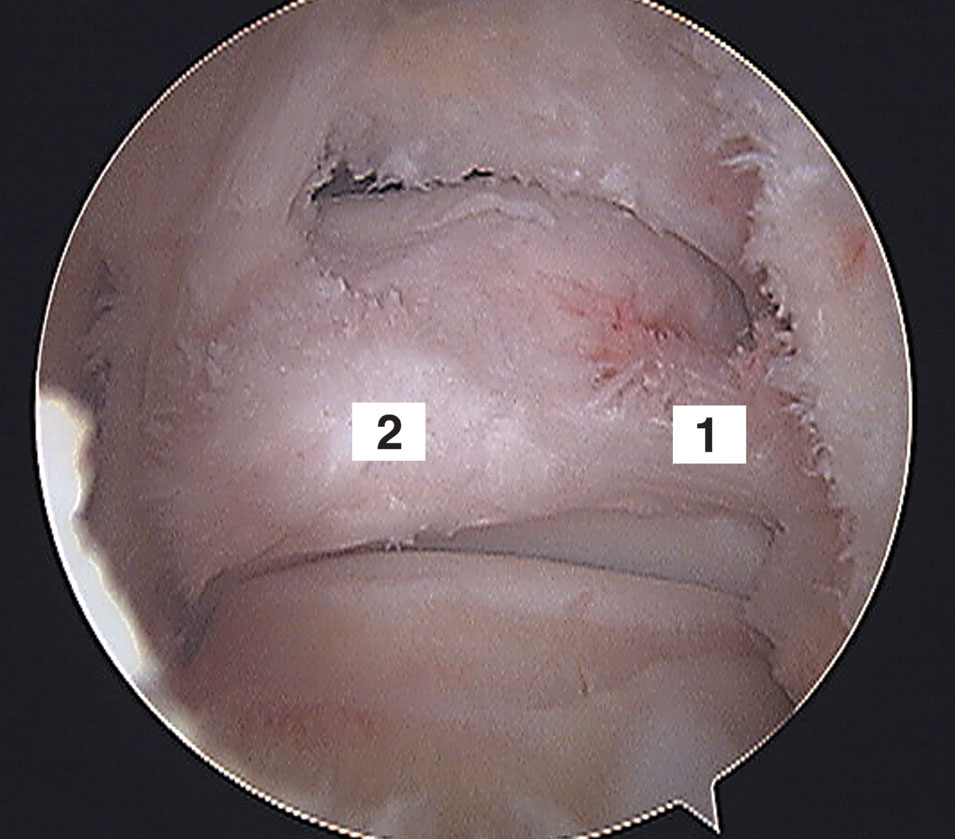

Figura 6: Vista artroscópica de 1) Ligamento talofibular posterior y 2) Os trigonum.

El ligamento talofibular posterior es un ligamento fuerte y grueso con forma trapezoidal localizado en un plano casi horizontal, tener en cuenta que es intracapsular y extrasinovial. Se origina en el maléolo lateral (fosa maleolar) y va hasta la parte lateral del astrágalo (Fig. 5). Es multifasicular por ese motivo sus fibras llegan: a la parte posterior del astrágalo y pueden llegar al tubérculo lateral del astrágalo, al os trigonum si está presente (Fig. 6), al proceso trigonal (Stieda) y otras contribuyen a formar el retináculo del tendón flexor largo del hallux (4) (Fig. 7). También llega hasta el componente profundo (ligamento transverso) del ligamento tibiofibular posterior y contribuye a formar el ligamento intermaleolar posterior, denominación propuesta por Paturet (8), también denominado “tibial slip” por Chen (9) y otros autores (Fig. 8, 9). Ayudando a formar el labrum existente en el margen posterior de la tibia.